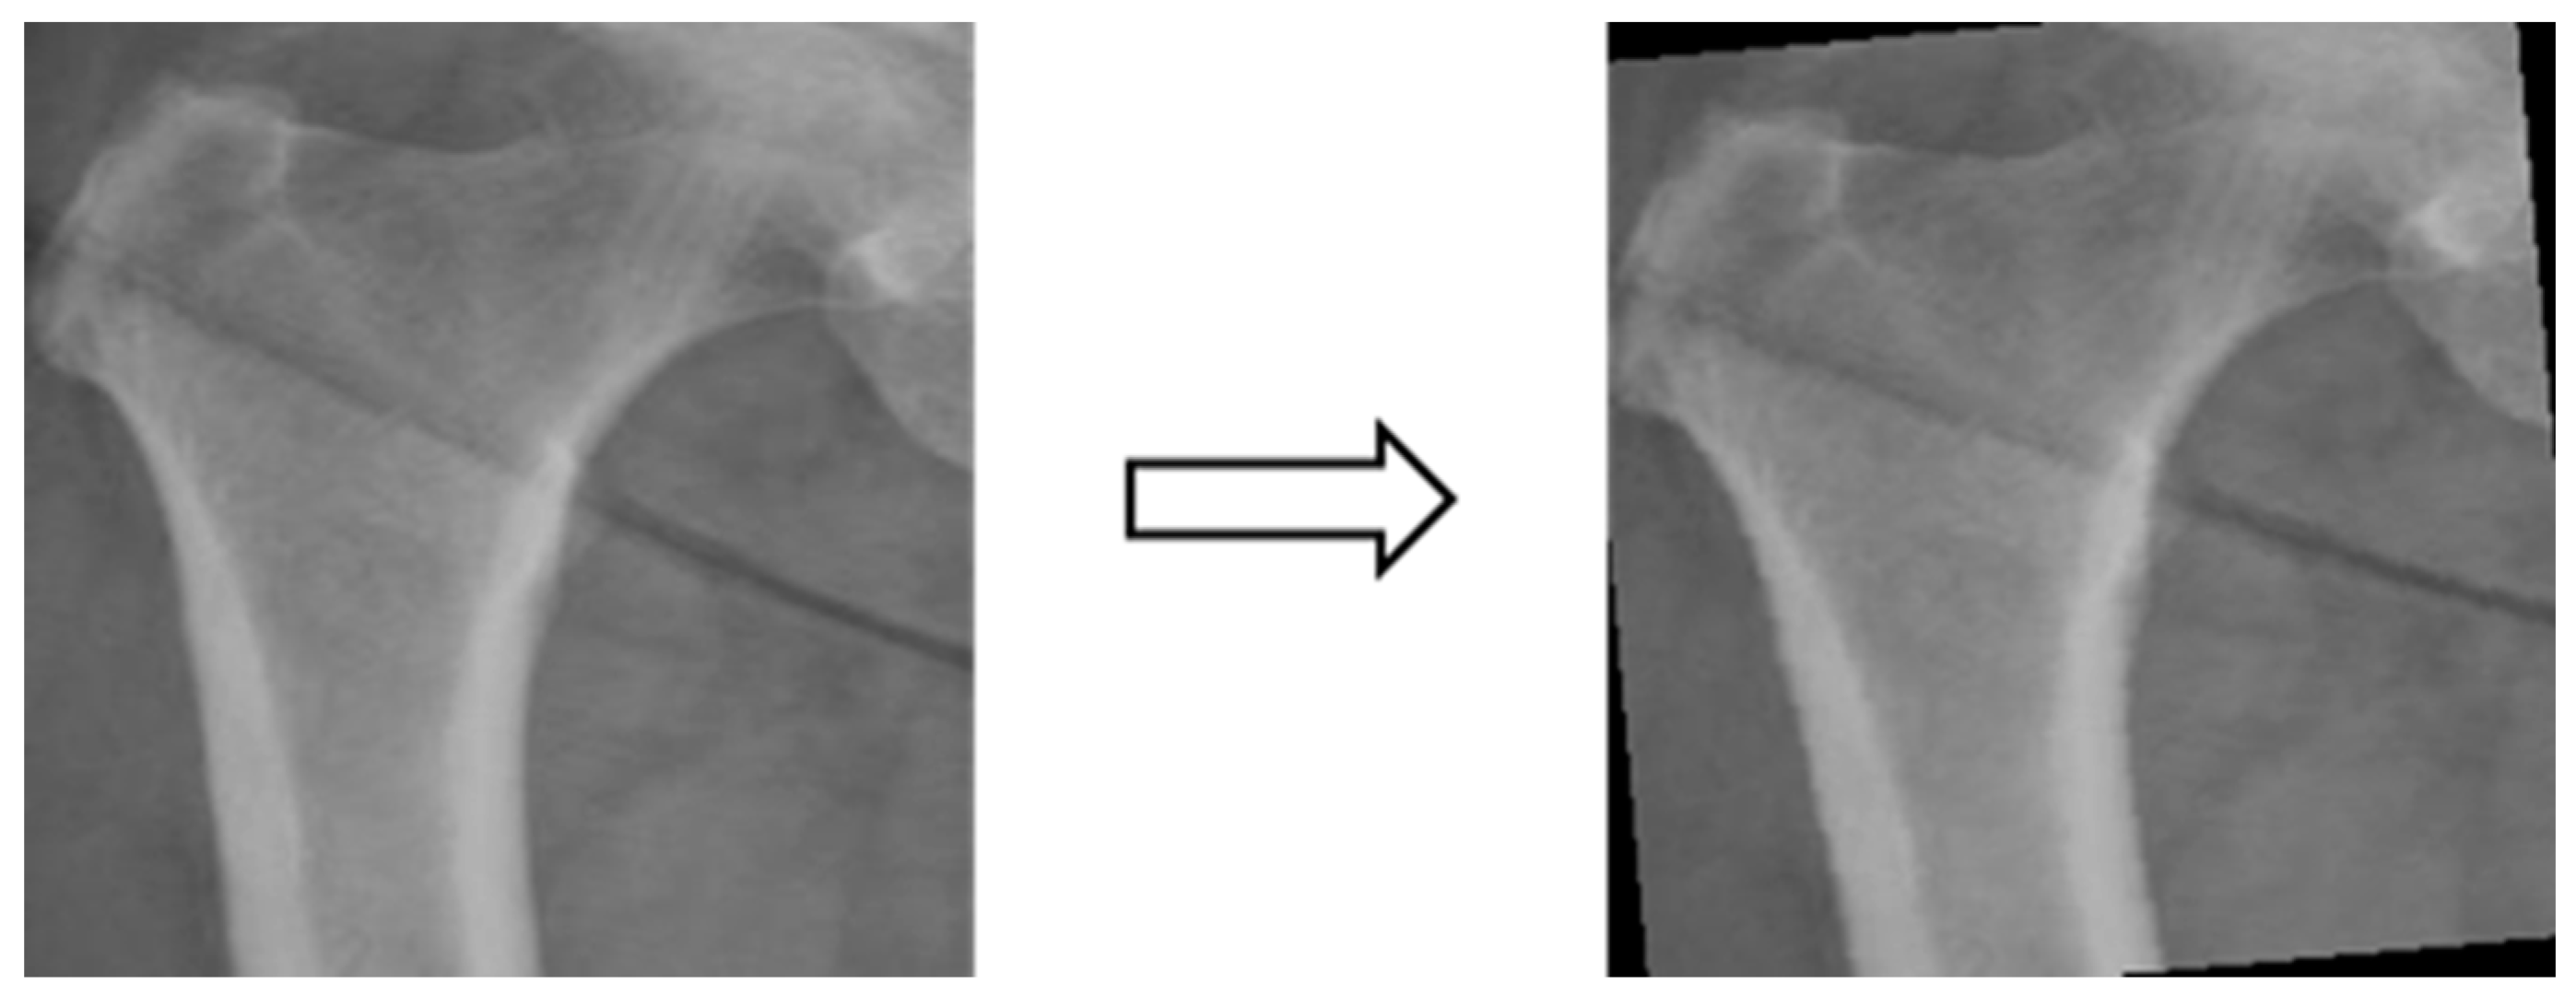

In this study, four parts of the image labeled X-ray images were used in image segmentation by feeding them into U-Net and U-Net++ models for training, and the bit depth of the four parts of the image was converted from the original 24 bits to 8 bits before the model training. The reason for choosing to use U-Net and U-Net++ is that their model structure is simpler, it does not need to spend a lot of time to filter out the remaining noise in the medical images, and it is less likely to form overfitting for a small number of image datasets. The binary segmentation prediction results obtained after training the models of U-Net and U-Net++ are shown in Figure 3 below.

3.3.3. Image matting

Based on the four parts of the image segmentation of the binary image and the original X-ray image together, the original X-ray image only retains the part of the image segmentation as shown in Figure 4; the other non-part of the contour of the background to remove, the image de-behind the hope that it can enhance the accuracy of the classification of the depth of the learning process, and then the image classification will be segmented images and not segmented images will be compared.